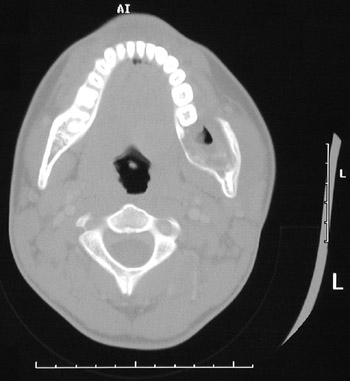

| This head CT scan in "bone window" demonstrates an ameloblastoma expanding the left mandibular ramus of a teenage male. Note the facial asymmetry. In the view below, this neoplasm extends to the superior ramus (and there is some scattering of x-rays from an earring on the right). |